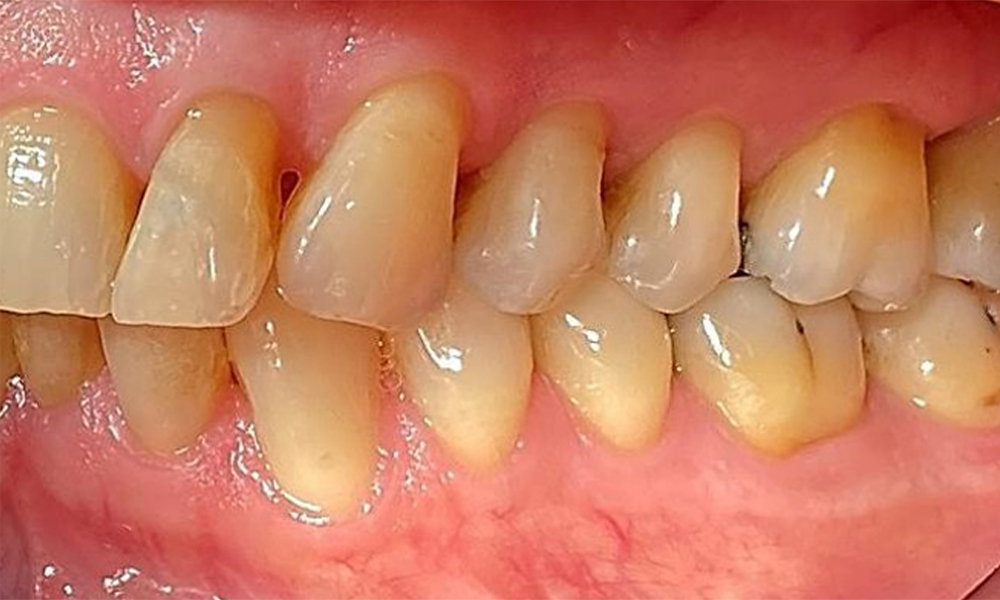

Lateralansicht rechts. Verlust der interdentalen Papillen. © Dr. R. Krapf

Abb. 3 Lateralansicht rechts. Verlust der interdentalen Papillen. © Dr. R. Krapf

Lateralansicht links mit Ansicht der Rezessionen. © Dr. R. Krapf

Abb. 4 Lateralansicht links mit Ansicht der Rezessionen. © Dr. R. Krapf

Der Patient hat eine Parodontitis Stadium II, Grad B (5). Die klinischen Sondierungstiefen liegen mit 1-3mm im physiologischen Bereich. Lokalisierte Sondierungstiefen finden sich an 17 und 27 jeweils mesiopalatinal mit 5mm. Es liegen generalisierte Rezessionen von 1-3mm vor mit partiellem Verlust der Interdentalpapillen (Abb. 2, Abb. 3, Abb. 4)